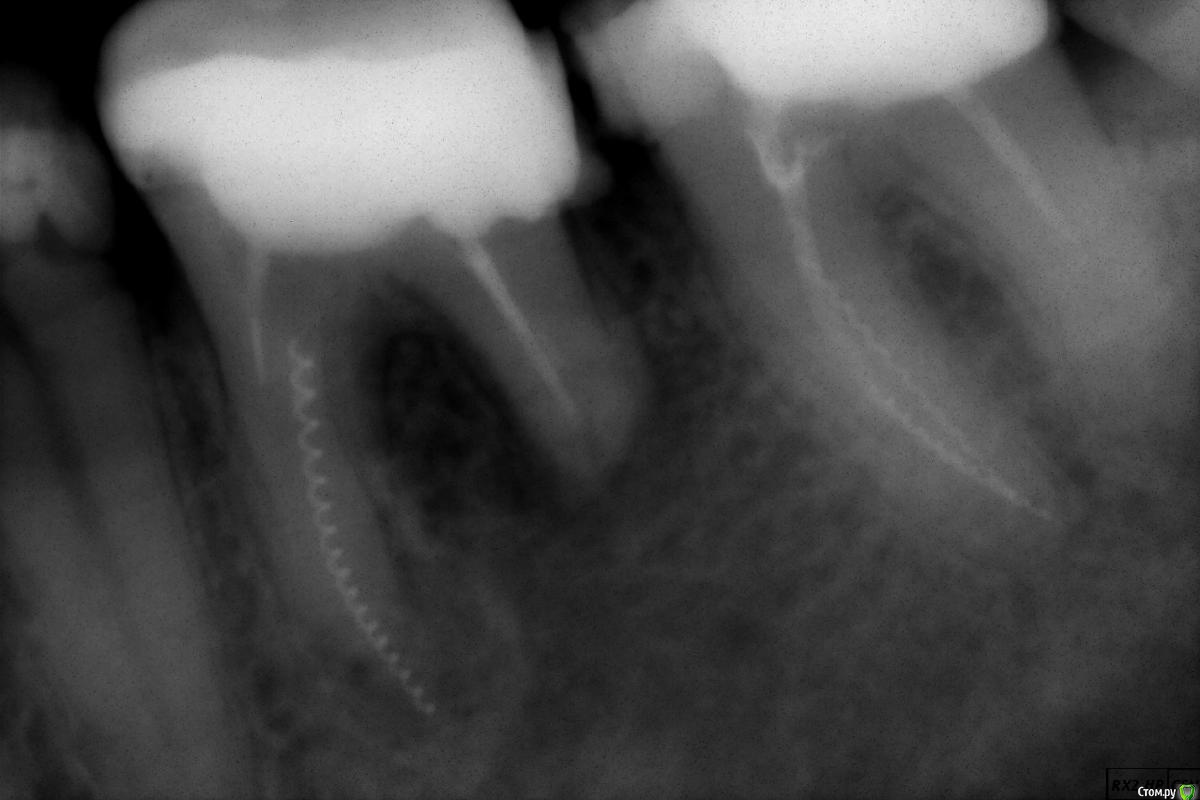

~~SERG~~ Опубликовано 26 декабря, 2016 Автор Поделиться Опубликовано 26 декабря, 2016 (изменено) А вот состояние 46 зуба на сегодняшний день. пошла резорбция корня со стороны 47, да и сам 47 просится на перелечивание, там в другой клинике тоже умудрились два инструмента сломать! И тоже мне ничего не сказали! PS если ктото решит что 46й зуб потреля большой кусок корня то "в защиту" прилагаю снимок 36го зуба - корень со стороны 37го короче чем со стороны 35. Изменено 26 декабря, 2016 пользователем ~~SERG~~ Ссылка на комментарий